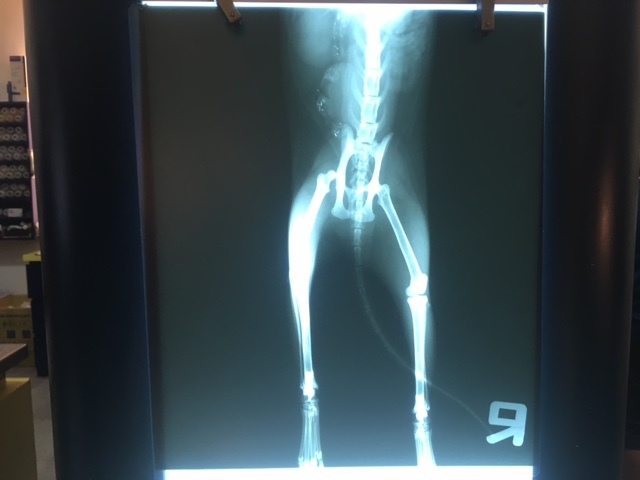

X光顯示左後腳髖關節脫位

血檢貧血PCV 22% 當天打了EPO造血針和鐵劑

5/19開刀切除脫位骨頭 也順便拔牙

術後再次拍X光確認手術後骨頭狀況

並且複驗血檢 PCV上升到34%